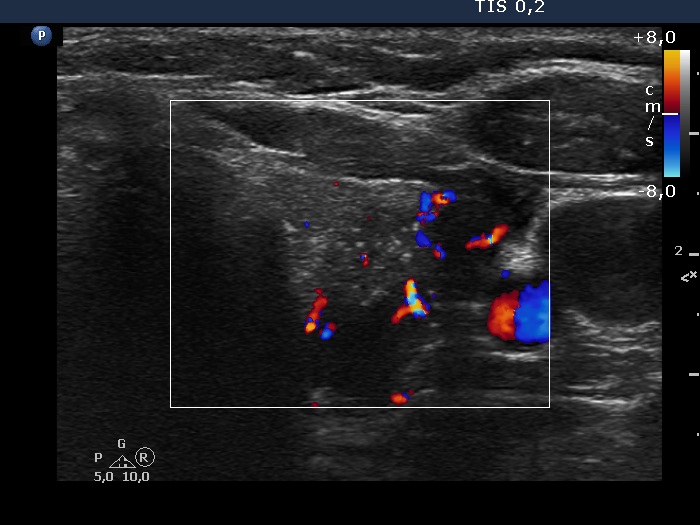

100 consecutive cases of papillary cancer - case 076 (ultrasonographic picture 13)

Right lobe, longitudinal scan

Left lobe, another transverse scan, color Doppler mode. The lesion shows irregular intranodular vascularization.